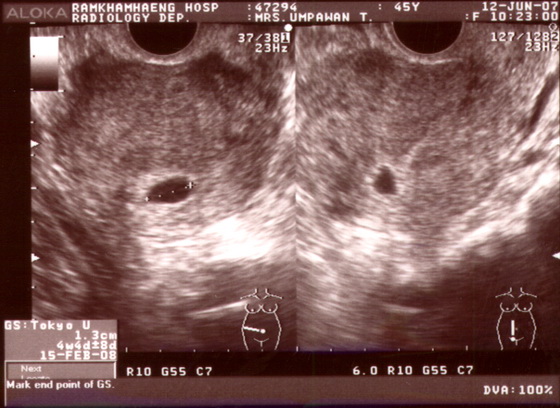

หญิงไทยคู่อายุ 45 ปี ขาดประจำเดือนประมาณ 1 เดือนครึ่ง. ผู้ป่วยมีอาการปวดท้องและมีเลือดออกทางช่องคลอด. การตรวจปัสสาวะพบหลักฐานบ่งชี้การตั้งครรภ์. การตรวจภาพถ่ายทางรังสีปรากฏดังภาพที่ 3.

ภาพที่ 3. ภาพถ่ายทางรังสีของผู้ป่วยรายที่ 3.

1. Ultrasonogram ของมดลูกผ่านทางช่องคลอด.

2. ปรากฏเงาคล้ายถุงน้ำในโพรงมดลูกขนาด 1 ซม. คำนวณเข้าได้กับการตั้งครรภ์ประมาณ 4 สัปดาห์ 4 วัน ไม่ปรากฏเงาคล้ายตัวเด็กหรือจุดการตั้งครรภ์ ที่จะเจริญไปเป็นตัวเด็ก.

3. Blighted ovum ส่อการตั้งครรภ์ที่ไม่มีตัวเด็ก. วินิจฉัยแยกโรคคือ ระยะเริ่มแรกของการตั้งครรภ์ แต่ยังไม่มีตัวเด็ก อาจตรวจ ultrasonogram ซ้ำอีก 7-14 วัน ทั้งนี้ขึ้นอยู่กับอาการของผู้ป่วย.